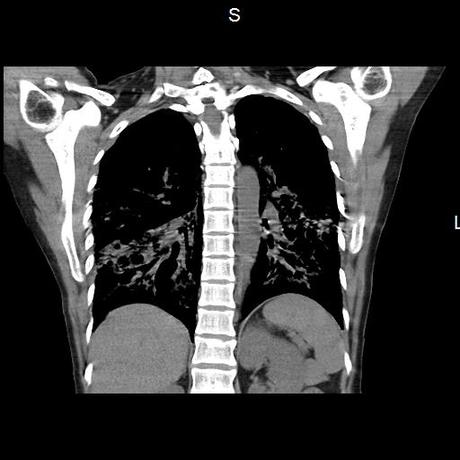

Se realiza volumen de tórax en fase simple, desde los opérculos torácicos hasta los hemidiafragmas, observándose:

El parénquima pulmonar con areas parcheadas difusas en vidrio despulido combinadas con otras areas hipodensas de baja atenuación debidas a atrapamiento aéreo y engrosamiento intersticial y zonas de fibrosis de predominio en lóbulos medios e inferiores de ambos pulmones.

- LOS HALLAZGOS PUEDEN ESTAR EN RELACIÓN A NEUMOPATIA INTERSTICIAL PROBABLE ETIOLOGIA HIPERSENSITIVA VS AUTOINMUNE/BACTERIANA/FUNGICA.